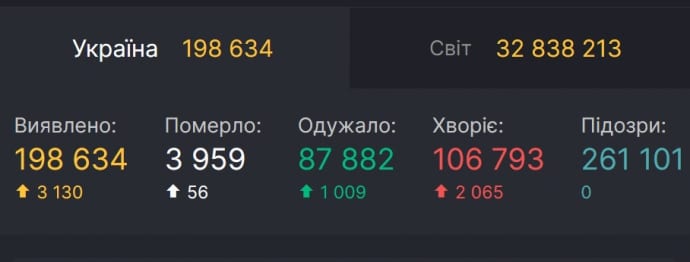

В течение субботы, 26 сентября, в Украине обнаружили еще 3 130 случаев COVID-19. Об этом сообщает Совет нацбезопасности и обороны, передает корреспондент «Наше Місто».

Зафиксировано 56 летальных случаев за этот период (сутками ранее – 76), выздоровели 1009 пациентов (сутками ранее – 1740). С начала эпидемии в стране выявили 198 634 инфицированных коронавирусом, умерли 3959 человека, выздоровели 87 882 украинца.